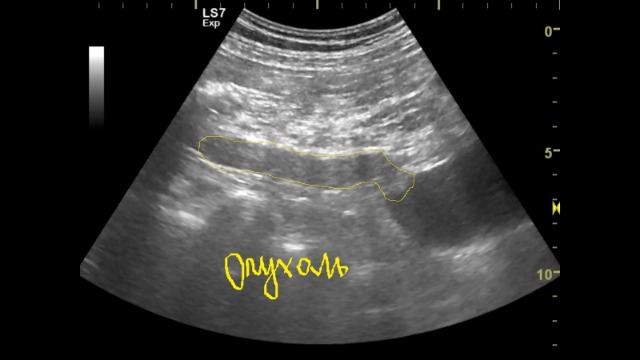

видно как опухоль распространяется в лоханку